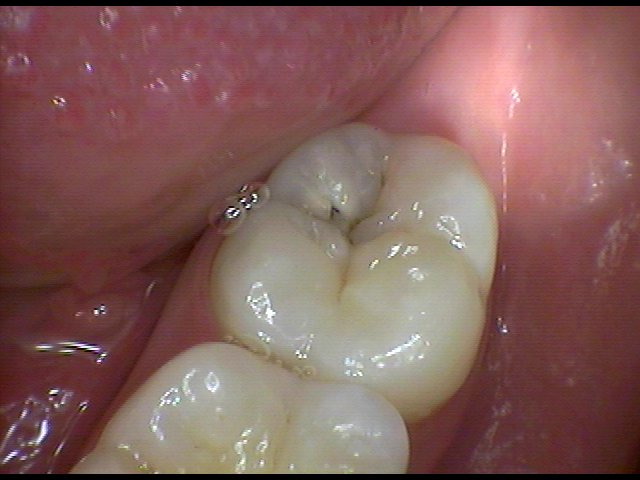

Diş çürüğü nedir? Diş çürükleri daha çok koyu renklenmelerle birlikte görülen oyuklar olarak algılanmaktadır. Önlenebilir bir hastalık olmasına karşın dünyada diş çürüğü deneyimi yaşamayan çok az insan vardır. Dişler neden çürür? Ağızda bulunan bakterilerden oluşan bakteri plağı, şekerli ve unlu yiyeceklerin ağızda kalan artıklarından asit oluşturabilmektedir. Bu asitler, dişlerin mineral dokusunu çözerek dişin minesinin bozulmasına ve sonuçta da diş çürüğünün başlamasına ve dişhekimlerinin kavite dedikleri oyuklara neden olmaktadırlar. Kimlerde daha çok çürük olur? Şekerli ve unlu yiyeceklerle bakterilerin buluşması sonucunda çürükler oluştuğuna göre herkes için bir tehlike var demektir. Ancak beslenmelerinde karbonhidratlı ve şekerli yiyeceklerin oranı çok yüksek olanlar bir de sularında florür oranı çok düşükse çok daha fazla çürük tehlikesi altındadırlar. Bakteri plağı tarafından oluşturulan asite karşı tükürük doğal bir savunma mekanizması oluştursa da tek başına çürüğü önleyemez.Tükürük akışını ve miktarını azaltan hastalıklar ya da ilaçlar da çürük oluşumunu hızlandırmaktadırlar. Bu nedenle de dişhekimleri tükürük akışını arttırdığı için şekersiz sakızları sıklıkla önerirler. Diş çürüğü önlenebilir mi? Evet. 1. Sabah kahvaltısından sonra ve akşam yatmadan önce dişlerin fırçalanması ve hergün diş ipliğinin düzenli kullanılması en etkili yoldur. Yiyecek artıkları en çok dişlerin çiğneme yüzeylerindeki girintilerde ve dişlerin birbirine değdiği ara yüzeylerde biriktiği için, diş fırçaları küçük başlı seçilmelidir. Dişlerin iç yüzeyleri, dış yüzeyleri, çiğneyici yüzeyleri ve dilin üstü fırçalanmalı ve ara yüzlerde diş ipliği kullanılmalıdır. Fırçalar, orta derecede sert ya da yumuşak kıllı olmalı ve belirli aralıklarda değiştirilmelidirler. Fırça kıllarının aşınmamış olması ve bakteri taşımayacak bir şekilde muhafaza edilmesi gerekmektedir. Asla başkasının diş fırçası kullanılmamalıdır. Diş fırçalama sırasında florürlü bir diş macunu kullanılarak, florürün diş çürüğünü önlemedeki rolünden yararlanılmalıdır. Florürlü macunlara yardımcı olarak aynı zamanda ağız kokusunu gidererek ferahlık ve temizlik hissi veren florürlü gargaralar da kullanılabilir. 2. Şekerli yiyecekleri ana öğünlerde tüketmeye çalışmak ve yemek aralarında birşey yememeye gayret etmek de diğer bir önlemdir. 3. Dişhekimine muntazam aralıklarla başvurmak bir çürüğü önlemek ya da erken yakalamada en iyi yoldur. Ayrıca sıcak ve soğuğa duyarlı dişler ya da ağrılı dişlerde veya tebeşirimsi renkte olan başlangıç çürükleri, kahverengi renklemeler ve oyuklar gibi durumlarda vakit geçirilmeden hekime başvurulması tedavinin şeklini değiştirecek ve zorluğunu azaltacaktır.  .jpg)